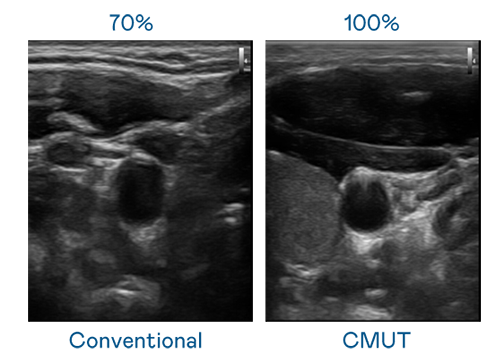

CMUT 技术是一种用电容式微机电元件来产生超音波讯号的技术。与传统 PZT 压电式技术相比,CMUT 频宽增加 30%,更宽频的超音波讯号让影像解析度大幅提升,是实现高影像品质医疗超音波扫描、促进精准医疗发展的关键技术。

超音波影像的解析度高低,首先取决于探头能发出的讯号频宽。xcsports CMUT 可提供高清晰的超音波讯号,提供高频宽、高灵敏度、影像纹理细节更高的超音波影像,协助医护人员缩短影像判读时间及利用精准的医疗影像进行诊断。